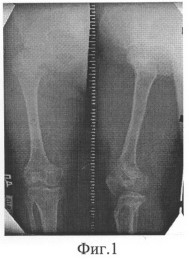

Больная М.,13 лет, поступила в клинику с диагнозом: Ахондроплазия, низкий рост (фиг.1). Для увеличения размеров конечностей больной выполнена операция: двойные остеотомии бедер, остеосинтез аппаратом внешней фиксации.